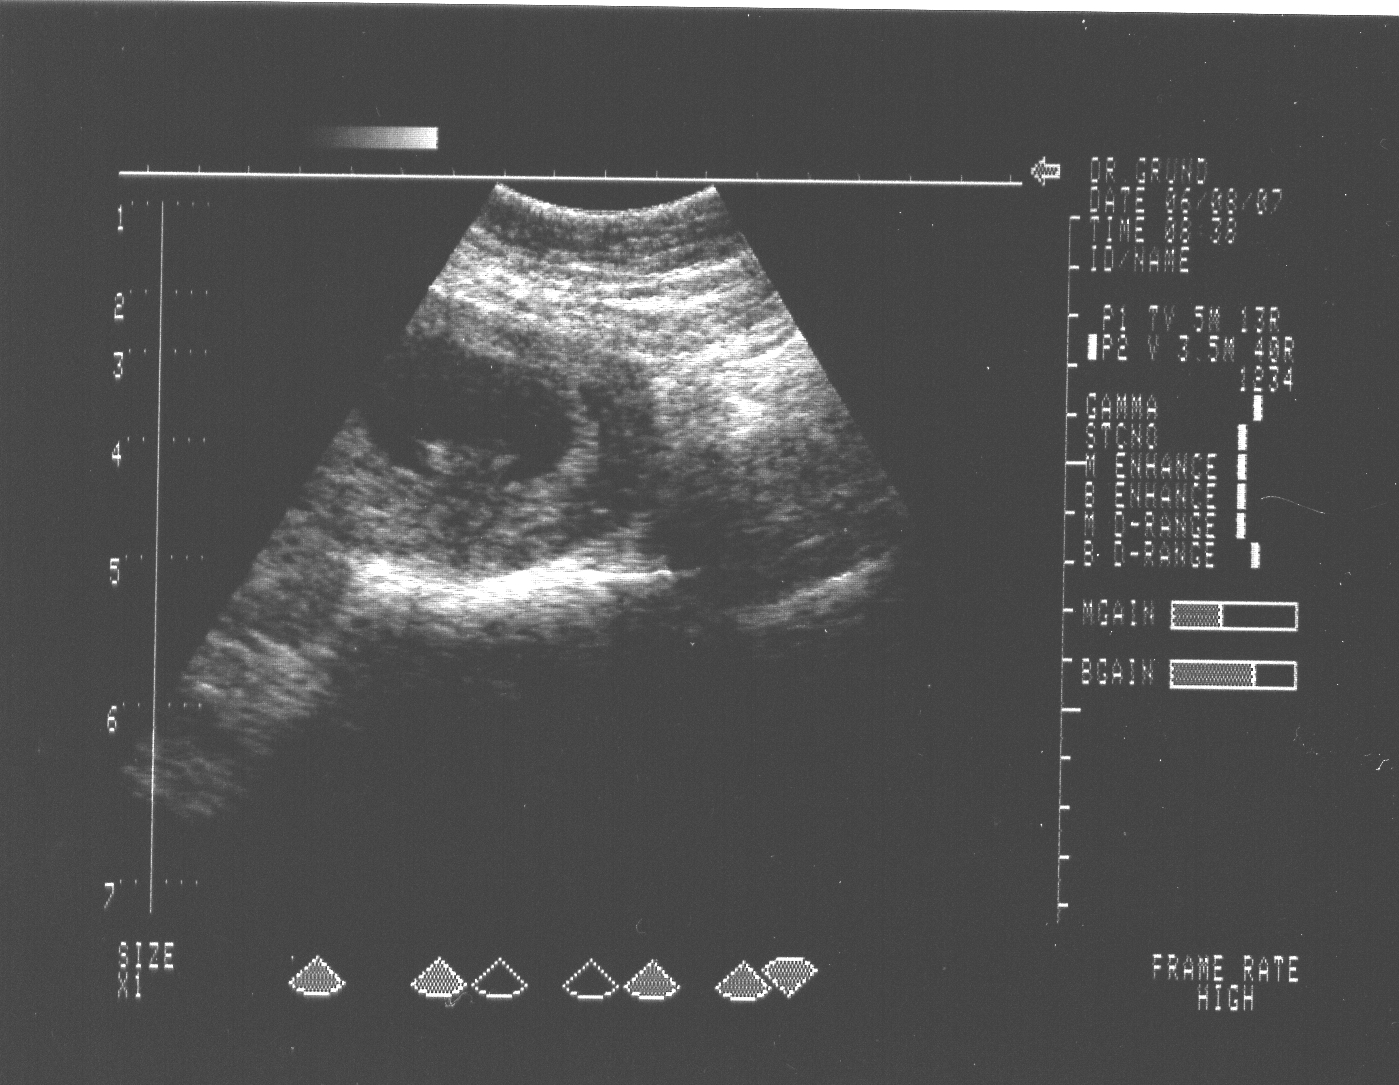

Schön,dass mit dem Krümel alles in Ordnung ist. Das beruhigt doch ungemein,oder? Aber man kann doch schon was auf dem Bildchen erkennen und warte mal,ratzfatz ist das kleine Menschlein komplett zu sehen.